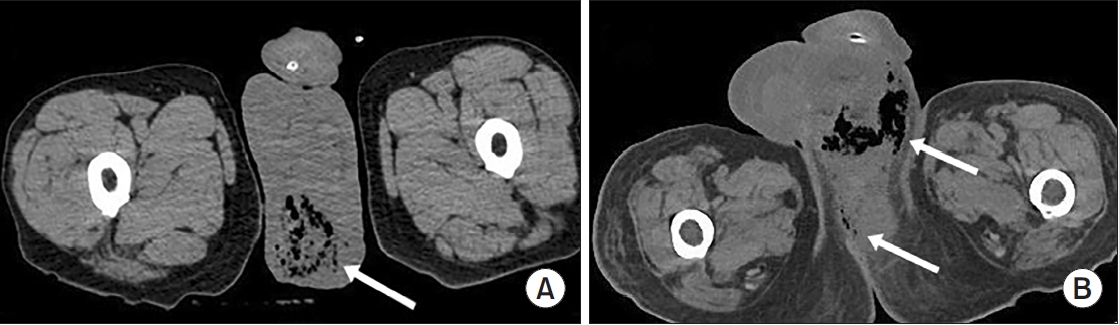

Clinical Characteristics and Risk Factors of Fournier Gangrene: A 15-Years Multicenter Retrospective Study in Korea

Fournier gangrene (FG) is a rare but life-threatening necrotizing infection requiring prompt recognition and intervention. This multicenter study aimed to investigate the clinical characteristics, treatment outcomes including mortality, and risk factors associated with death among patients with FG over the past 15 years in Korea. Materials and Methods: We retrospectively reviewed 84 patients diagnosed with FG between 2008 and 2022 across 7 hospitals. Demographics, comorbidities, laboratory findings, and clinical outcomes were analyzed. Mortality-related risk factors were assessed using univariate and multivariate logistic regression analysis.

The mean age was 58.1±15.9 years, and 95.2% of patients were male. Diabetes mellitus (42.9%) and hypertension (36.9%) were the most prevalent comorbidities. Sepsis developed in 38.1% of patients, and the overall mortality rate was 14.3%. In univariate analysis, age ≥70 years, low body mass index, diabetes mellitus, low hemoglobin, low hematocrit, high respiratory rate, and Fournier gangrene severity index (FGSI) ≥9 were significantly associated with mortality. After data correction and multivariate adjustment, diabetes mellitus (odds ratio [OR], 39.61; 95% confidence interval [CI], 2.39–656.32; p=0.010) and respiratory rate (OR, 1.44; 95% CI, 1.09–1.91; p=0.011) were identified as independent predictors of mortality. FGSI≥9 demonstrated borderline association with mortality (p=0.08), indicating its potential clinical relevance.

In this multicenter Korean cohort, the mortality rate of FG remained substantial at 14.3%. Diabetes mellitus and elevated respiratory rate were independent predictors of mortality, while FGSI≥9 demonstrated a borderline yet clinically meaningful association, suggesting its role as a useful severity indicator in early risk stratification.